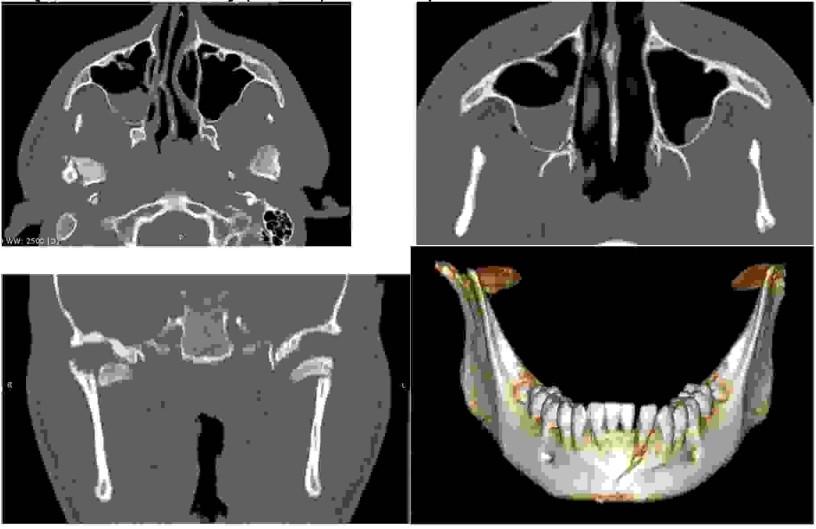

Pacjent (16 lat) uległ wypadkowi, jeżdżąc na hulajnodze. Doznał urazu okolicy bródkowej, gdzie ma ranę oraz urazu prawego policzka: zgryz otwarty całkowity od chwili urazu. Rozchwiany siekacz boczny dolny. Stan ogólny dobry: nie ma innych obrażeń ciała. Poniżej są obrazy z tomografii komputerowej wiązki wachlarzowej (FBCT). Wskaż prawidłowe leczenie:

Pytanie 76